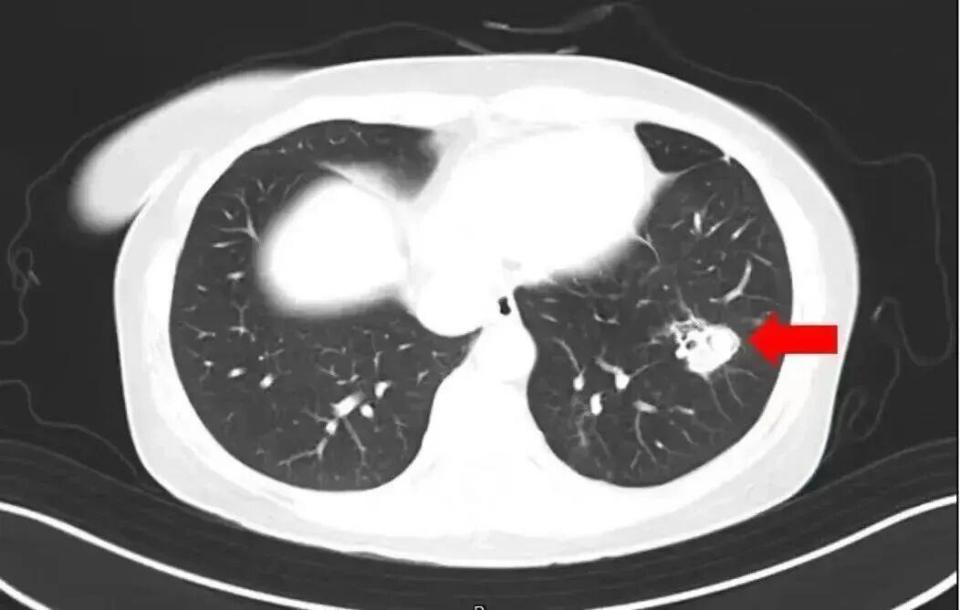

• 2025年1月,江苏扬州的张大爷为迎接春节开始大扫除,清扫过程中不慎吸入大量灰尘和霉菌孢子,导致哮喘发作。张大爷随即服用了常备的哮喘治疗药物,可症状反而逐渐加重。经检查,张大爷的肺部出现感染,确诊为肺曲霉病。